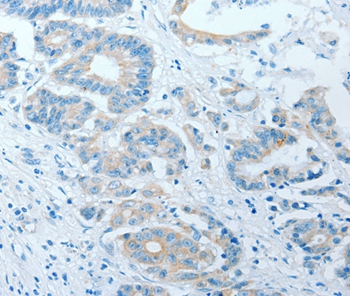

分类: 科研抗体货号: P42772别名: ILT4; LIR2; CD85D; LIR-2; MIR10; LILRA6; MIR-10应用: IHC反应种属: Human